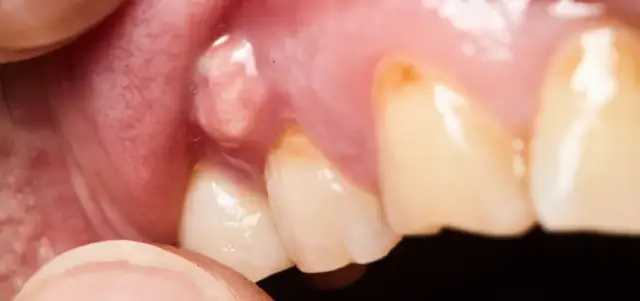

Poznaj objawy włókniaka jamy ustnej i dowiedz się, jak je rozpoznać. Zrozum, kiedy warto skonsultować się z lekarzem w przypadku zmian.